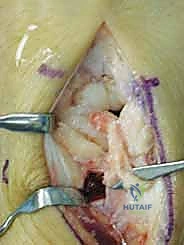

1. يقوم الدكتور هطيف بإجراء قطع عظمي دقيق (Osteotomy) في العظم الكبير.

2. يتم إزالة شريحة صغيرة جداً من العظم (عادة بضعة مليمترات فقط).

3. يتم إعادة تثبيت العظم الكبير باستخدام مسامير دقيقة (Screws) أو دبابيس معدنية (K-wires).

4. النتيجة الميكانيكية: من خلال تقصير العظم الكبير، يتم نقل مسار توزيع القوة (Load Shift) بعيداً عن العظم الهلالي الضعيف، وتوجيهه نحو العظم الزورقي والعظام الأخرى. هذا الإجراء يمنح العظم الهلالي "مساحة للتنفس" والشفاء دون أن يتم سحقه تحت ضغط حركة اليد.